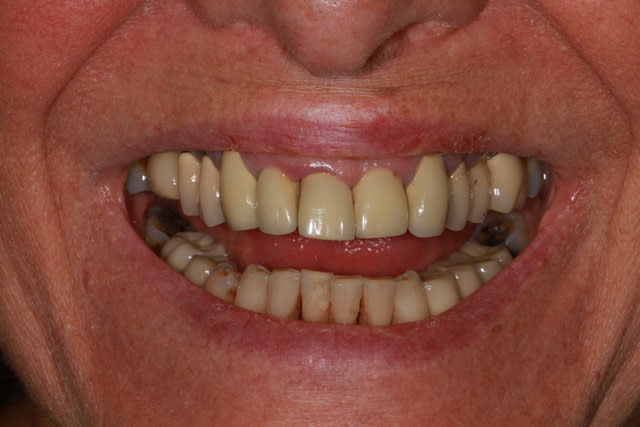

j'ai mis en rouge toutes les zones très malades, voir suceptibles d’être en fin de vie...

il te reste donc 1 canine et 3 incisives, plus l'implant...

C'est sûre que quand on voit la différence qu'il y a au niveau du parodonte entre la maxillaire sup. et le maxillaire inf., l'usure de certaines dents, et la mauvaise adaptation de certaines couronnes, on est fortement incité à penser à une cause iatrogène...